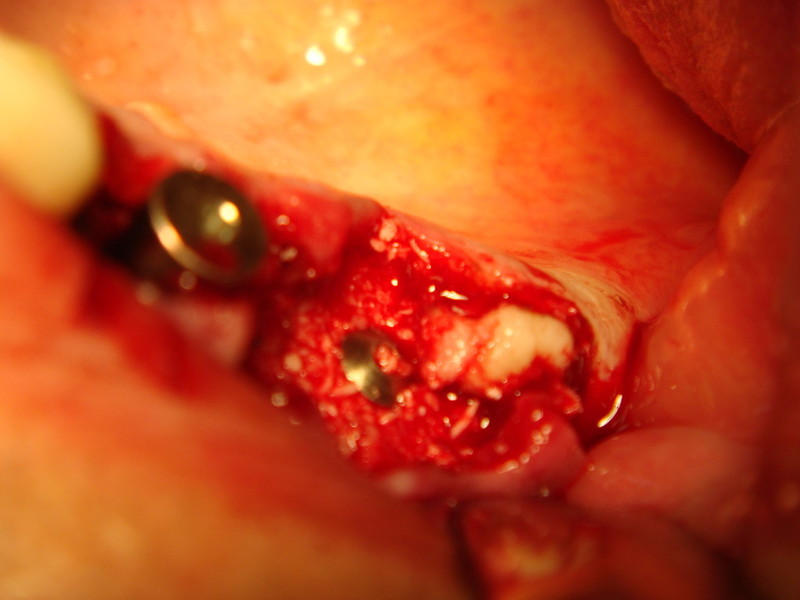

Implantologia avanzata con contestuale rimozione impianti e cisti

Impianti post-estrattivi complessi con innesto osseo

Impianti Post-estrattivi con innesto di osso e tessuto epitelio-connettivale

Estrazione di un canino incluso e contestuale inserimenti di impianto e innesto osso eterologo